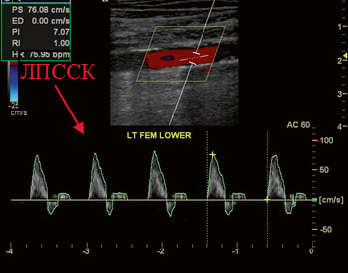

Определение ЛПССК для каждой исследуемой артерии проводилось в спектральном допплеровском режиме (рис. 2).

Рис. 2. Измерение лодыжечной пиковой систолической скорости кровотока в спектральном допплеровском режиме. Стрелкой указана допплеровская волна, по пику которой формируется скорость кровотока (см/с).

Среднее значение ЛПССК рассчитывалось как отношение суммы ЛПССК на ТАС и ЗББА, деленное на 2: "ЛПССКср=(ЛПССК (ТАС)"+ЛПССК (ЗББА))/2.

Например: ЛПССК (ТАС)=0 см/с, ЛПССК (ЗББА)=40 см/с, ЛПССК ср=(0+40)/2=20 см/с.